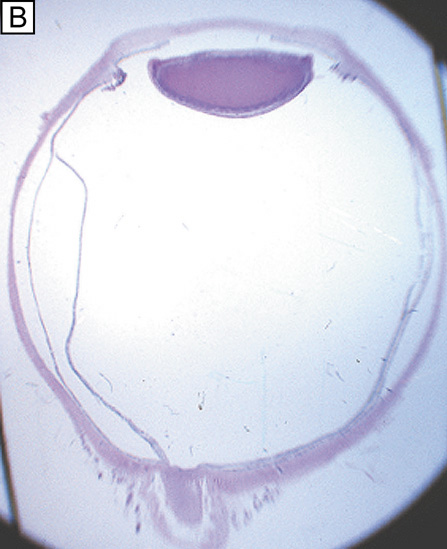

The cornea covers the anterior one-sixth of the total circumference of the globe (Fig. 1), whereas the sclera covers the remaining five-sixths. The cornea is a clear, transparent, colorless avascular structure richly supplied with sensory nerve endings that generally subserve touch and pain. There are no lymph vessels or other channels for bulk fluid flow. The interface between the corneal tear film and the ambient atmosphere provides roughly two-thirds of the refractive power of the human eye. The cornea itself is resilient, yet is described as viscoelastic in its response to stretching forces.

Fig. 1. (A) Diffuse illumination slit-lamp view of the human cornea. (B) Slit-beam illumination slit-lamp view of the human cornea shows an optical section of the tissue. Notice the slight light scattering that occurs in the tissue, mainly from cellular components in cornea. (C) Histologic diagram of the major cellular and extracellular matrix components of the human cornea (toluidine blue 25×).